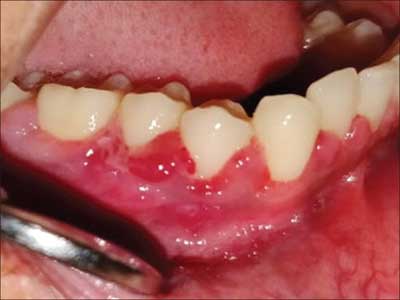

Your belly isn’t the only thing that’s swelling up these days. Your gums may also be extra tender, swollen, red, sensitive and prone to bleeding during pregnancy, especially when you brush and floss.

Your dentist may give you a diagnosis of pregnancy gingivitis; that is gum infection during pregnancy

During pregnancy, hormones get excited and can cause many problems in your body especially in your mouth, mostly during first trimester and third trimester. Hormonal changes during pregnancy can make your gums more vulnerable to plaque,

Leading to inflammation and bleeding. This is also called pregnancy gingivitis or gum disease.

Especially estrogen and progesterone; this two hormone are responsible for bleeding gum.